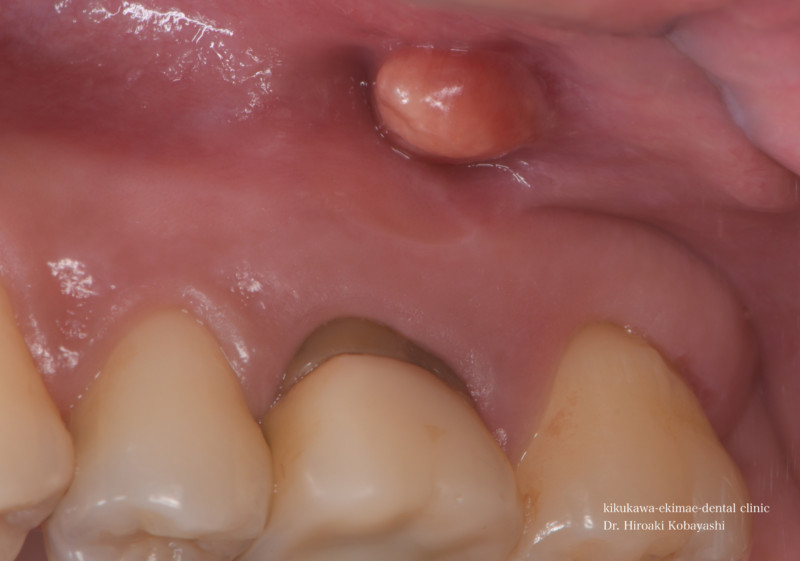

歯茎からオデキが出来たと来院されました。 CT撮影を行いますと、根の感染が見られました。感染の長期の放置により骨が溶けており、歯の保存が難しそうな状況でした。痛みもなく、特に生活に支障はありませんが、刻一刻と早期に歯を失う方向に進んでいます。おそらく、数年このままですと痛みもなくある日、ぐらぐらし、抜け落ちていたでしょう お話し合いの上、精密根管治療にて歯の保存を希望されましたので、治療を開始しました。   時間をかけ、顕微鏡を使用し感染の除去を行なっていきます。過去に根の処置を行なった時に入れたであろう薬剤や膿や出血が出てきます。 2時間程度のアポイントを3回お取りし、精密根管治療が完了しました。 オデキはなくなり、無事歯を残す事が出来ました。   CTにて経過を見ますと骨の再生が起きています 約6ヶ月〜程度かけて骨の再生が起こります。 リスク 極端に硬いものを噛むとかける可能性があります。 各種治療費はこちらから